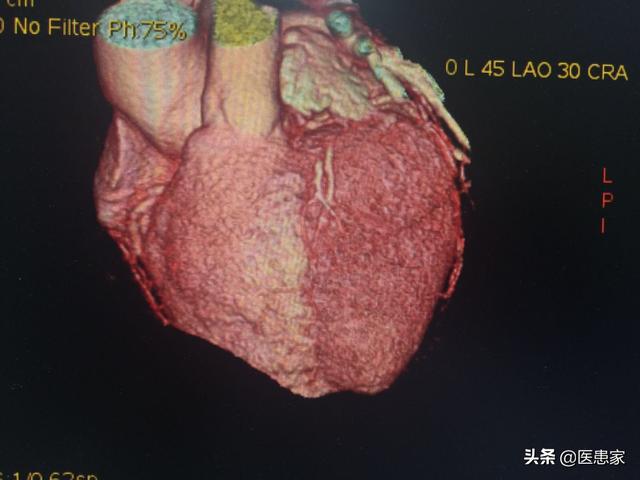

冠動脈造影検査は冠動脈疾患の診断を確定するためのゴールド・スタンダードですが、侵襲的な検査でもあり、患者さんにとっては有害な検査なので、他の検査のようにやりたいときにできるわけではなく、通常は専門医の判断がないと実施できません。

冠動脈造影検査は、患者が起きている間に行われ、(すべてがうまくいけば)10時間以内で終了するが、患者の血管が細く、位置を特定するのが困難な場合は、さらに時間がかかることがあるが、一般的には小手術のような検査と考えられている。

1、医師は患者の右手の動脈を穿刺し、すべての基本となるシースを入れる。

2、造影カテーテルはシースを通して心臓に送られる。

3、造影剤を造影カテーテルから注入し、X線透視で外から見る。

そのため、冠動脈造影は侵襲的な検査であり、あえて必要だと言う医師はいないし、実施するためには多くの条件を考慮する必要がある。